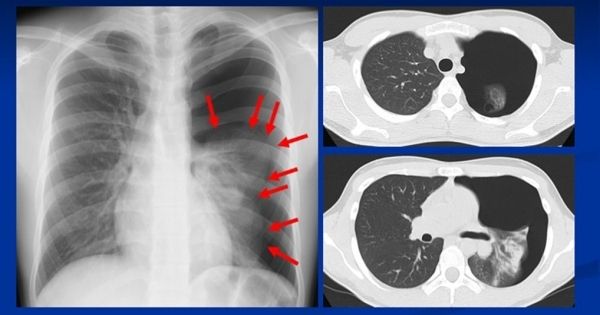

18歳男性=原発性自然気胸のX線写真。もやのような細い網目模様は肺の中に走る血管。向かって左の肺に比べると、右の肺の上半分に網目模様(血管)がないことが見て取れる。肺が矢印の位置まで押しつぶされてしまっている。右側の2枚のCT画像は、輪切りにした体内を写し出したもの。肺上部(上)と比べても、下部(下)は特にひしゃげているのがわかる

[写真 2/3枚目] 18歳男性=原発性自然気胸のX線写真。もやのような細い網目模様は肺の中に走る血管。向かって左の肺に比べると、右の肺の上半分に網目模様(血管)がないことが見て取れる。肺が矢印の位置まで押しつぶされてしまっている。右側の2枚のCT画像は、輪切りにした体内を写し出したもの。肺上部(上)と比べても、下部(下)は特にひしゃげているのがわかる